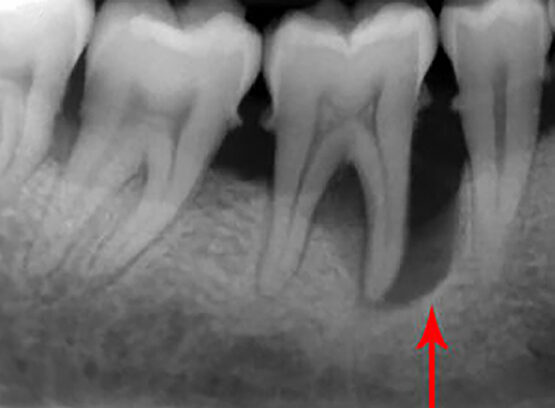

E' una branca dell'odontoiatria che si occupa delle patologie che affliggono i tessuti del parodonto, costituito da: gengiva, osso, cemento radicolare e legamento parodontale. Gengivite e parodontite sono le due malattie parodontali principalmente causate da batteri che accumulano tra dente e gengiva. Il trattamento dei tessuti che circondano il dente ne' assicura stabilita' e qualità ' nel tempo.